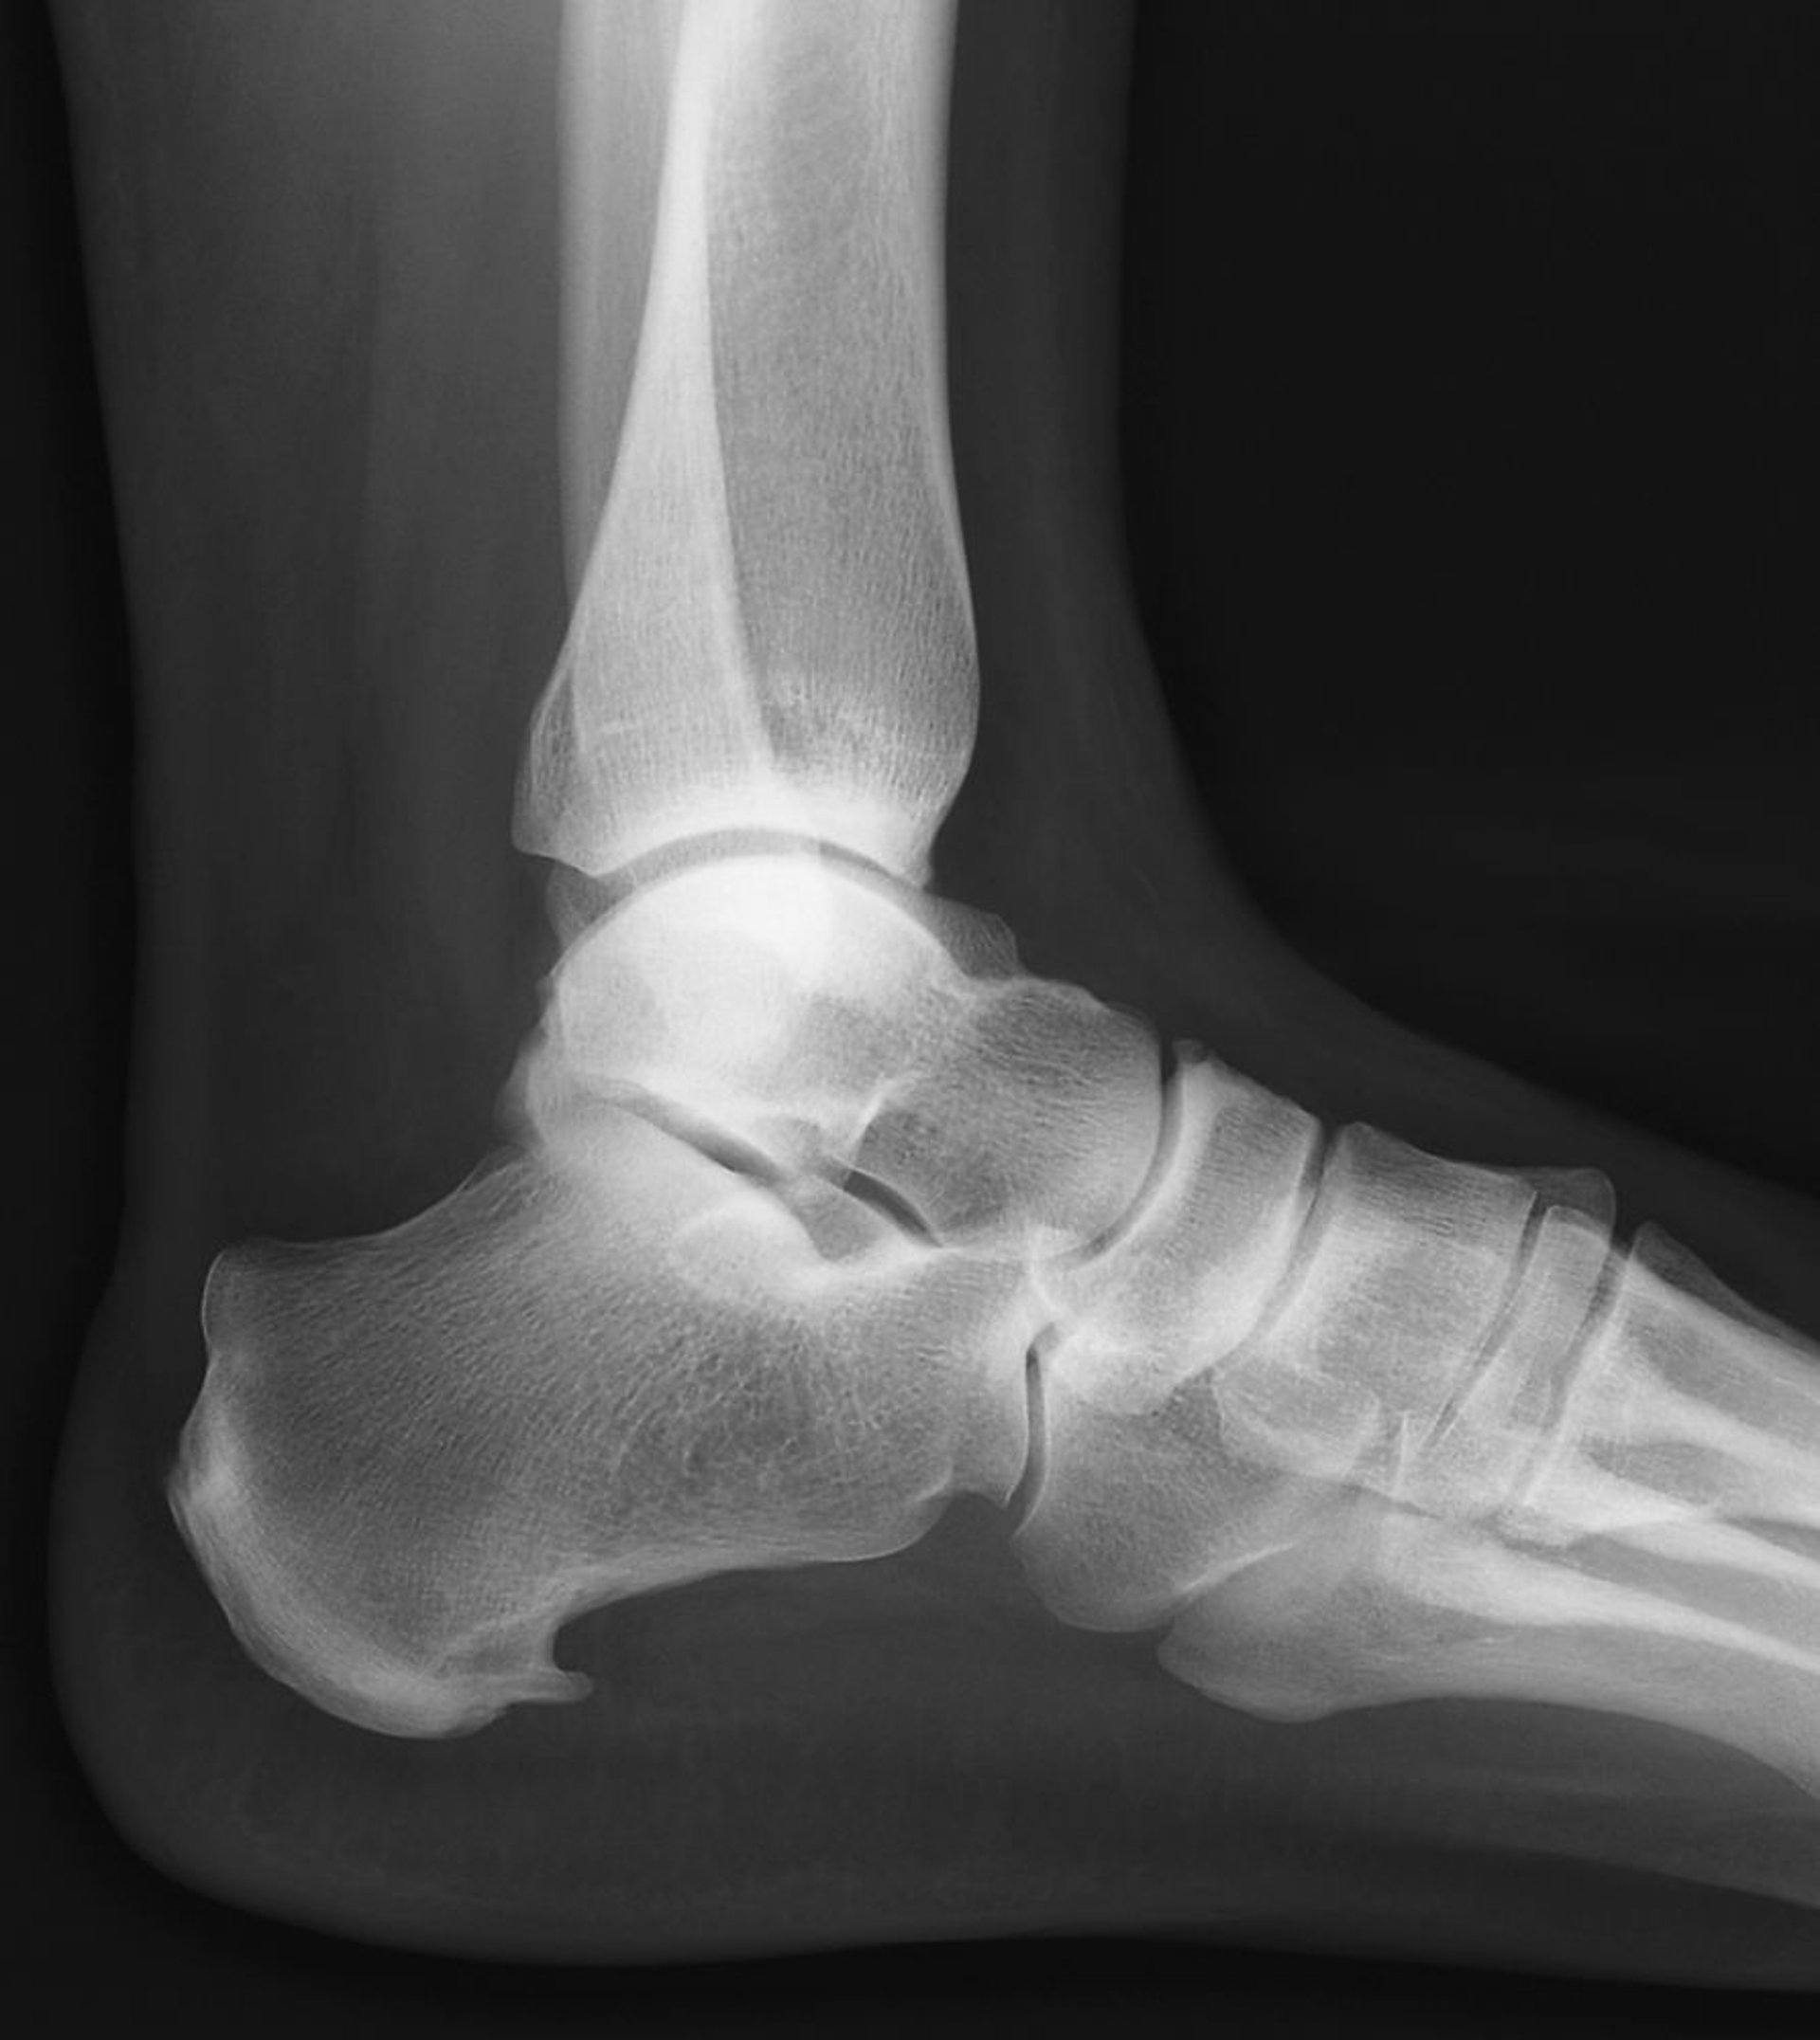

Пяточная шпора –это костный экзостоз, выпирающий вперед от основания пяточной кости.

ZEPHYR/SCIENCE PHOTO LIBRARY